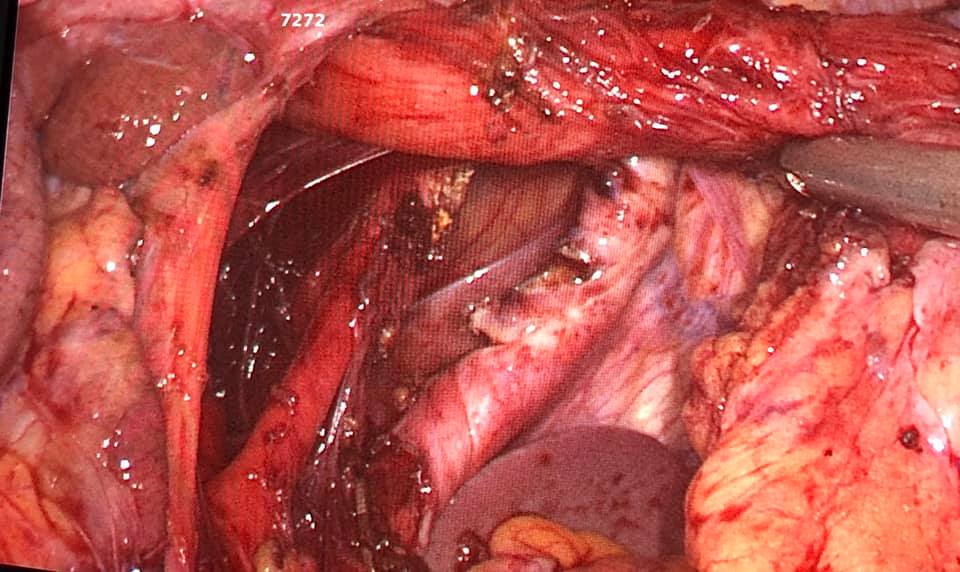

Laparoscopic total proctocolectomy and ileal pouch surgery for ulcerative colitis

Mr SR aged 40 was suffering from steroid resistant ulcerative colitis with severe bloody diahhorea 10-15 times a day with anemia and progressive weight loss not responding to medications. He underwent laparoscopic total proctocolectomy and ileal pouch surgery 2 years ago, performed by Dr. Phani Krishna Ravula. 2 years later on follow up He is now of all medication and cured of ulcerative colitis and back to job with excellent quality of life.